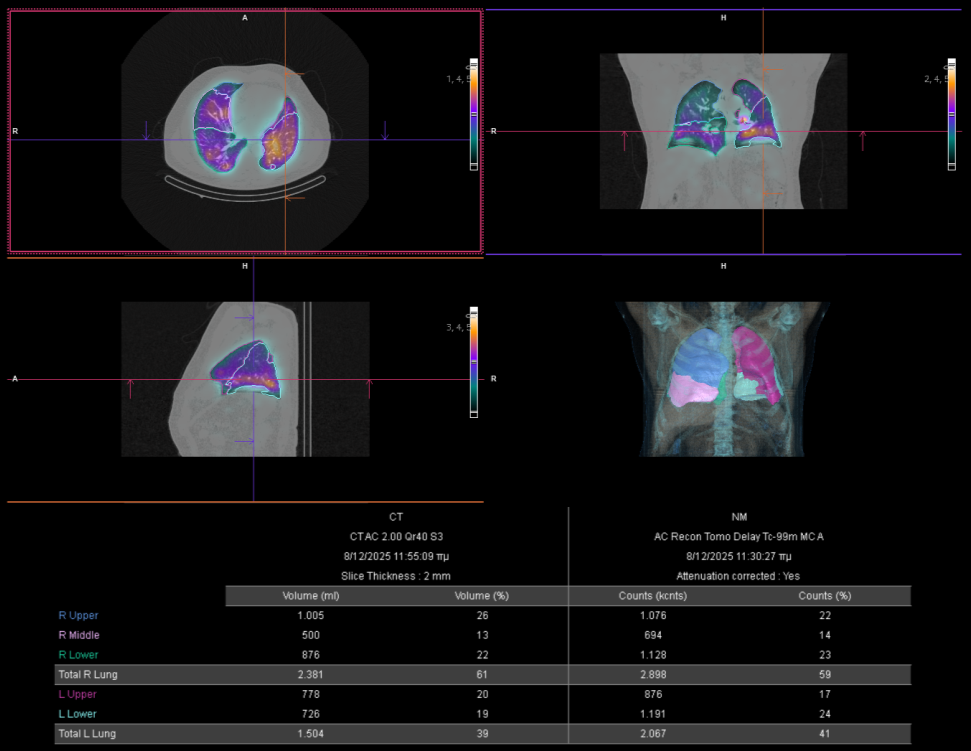

Η θεραπεία με Ύτριο-90 SIR-Spheres (Y-90) αποτελεί μια εξειδικευμένη τεχνική εκλεκτικού ενδοαρτηριακού εμβολισμού, η οποία στοχεύει αποκλειστικά τον όγκο μέσω των ηπατικών αγγείων, επιτρέποντας την εναπόθεση σωματιδίων που εκπέμπουν ραδιενέργεια τοπικά με ελάχιστη ακτινική επιβάρυνση στους υγιείς ιστούς. Η διαδικασία περιλαμβάνει λεπτομερή προθεραπευτικό αγγειογραφικό σχεδιασμό με αξιολόγηση της αγγειακής ανατομίας και χορήγηση ενός ιχνηθέτη για την ανίχνευση τυχόν διαφυγής (πχ. lung shunt), εξασφαλίζοντας μέγιστη ασφάλεια και εξατομίκευση. Η επιλογή της δόσης γίνεται πλέον με σύγχρονα υπολογιστικά μοντέλα δοσιμετρίας και εξειδικευμένα λογισμικά (όπως MIM ή SIR-TeX platform), τα οποία επιτρέπουν ακριβή αποτύπωση του όγκου της νόσου στο ήπαρ, υπολογισμό του πραγματικού tumor burden και εκτίμηση της απορροφούμενης δόσης τόσο στον όγκο όσο και στο υγιές ηπατικό παρέγχυμα. Μετά τη θεραπεία, πραγματοποιείται έλεγχος κατανομής της ακτινοβολίας (μέσω Bremsstrahlung SPECT/CT ή PET/CT), ενώ ακολουθεί στενή απεικονιστική και κλινική παρακολούθηση για την αξιολόγηση της ανταπόκρισης, την εκτίμηση τυχόν τοξικοτήτων και τον σχεδιασμό επόμενων βημάτων στην ογκολογική στρατηγική του ασθενούς. Πρόκειται για μια ιδιαίτερα αποτελεσματική θεραπευτική επιλογή σε πρωτοπαθείς ηπατικούς όγκους και σε ηπατικές μεταστάσεις, ειδικά όταν οι συμβατικές θεραπείες έχουν περιορισμένη αποτελεσματικότητα ή δεν είναι πλέον εφικτές.

Με τη SPECT‑CT ποσοτικοποίηση υπολογίζουμε απορροφούμενες δόσεις σε όγκους και όργανα‑στόχους (νεφροί, σιελογόνοι, ήπαρ, μυελός κ.ά.). Αυτό: